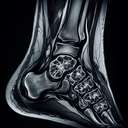

МРТ гомілково-ступневогу суглобу

МРТ гомілково-ступневого суглоба – це неінвазивний метод діагностики, який використовує магнітні поля та радіохвилі для створення детальних зображень м’яких тканин, кісток та суглобів. Ця процедура є безпечною та безболісною і не використовує радіацію. Показання для проведення МРТ гомілково-ступневого суглоба можуть включати: - Виявлення розривів зв'язок або сухожиль...